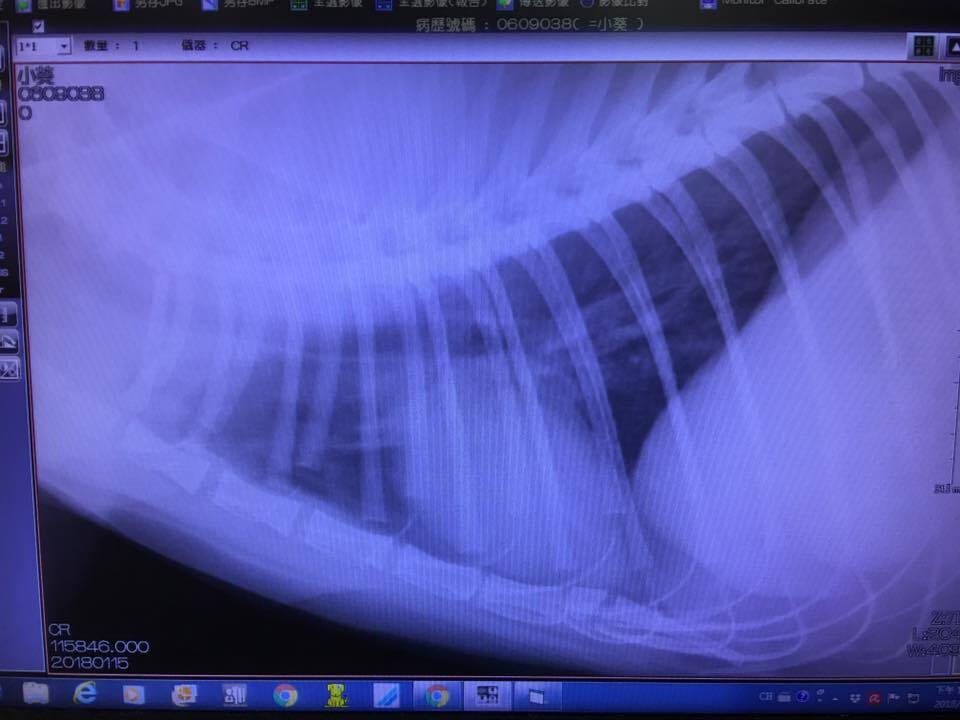

抽血檢查都沒問題,呼吸聲音大的問題已排除鼻塞問題,拍胸腔x光片檢查發現有肺部輕微發炎;口服藥有調整,有加抗生素與氣管擴張藥劑,須配合每日噴霧治療

抽血結果顯示其他都正常只有球蛋白偏高,但還在可接受範圍;拍胸腔X光看到肺臟狀況有好很多,醫師這次會把類固醇加回去但是「三天」吃一次,噴霧仍然繼續噴